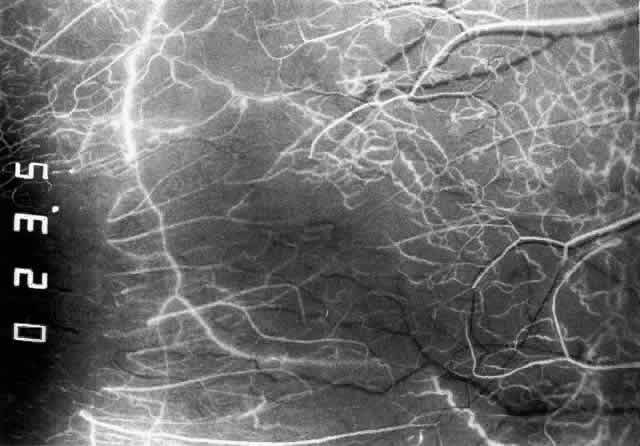

The anterior ciliary arteries run radially toward the limbus within Tenon's capsule, giving few, if any, branches until they reach the anterior part of the globe. Their positions are very variable, and they do not always follow the rectus muscles. They bifurcate 2 to 5 mm behind the limbus, and each division runs forward and circumferentially to anastomose with a branch from an adjacent artery. This results in an anterior episcleral arterial circle (Figs. 3 through 5). The divisions of the anterior ciliary arteries are typically superficial at their origins but run deeper at their anastomoses. They occasionally dip too deep to be seen in fluorescein angiograms (Fig. 6).

Fig. 3. Normal superior anterior segment angiography in a 35-year-old man. The main anterior ciliary arteries have filled, branching at or adjacent to the limbus to fill the limbal arcade, the recurrent branches of which are passing backward to fill the episcleral and conjunctival vessels. The episcleral circle here is superficial, and the anastomotic vessels are readily visible. There is a close resemblance to the vascular pattern in Figure 1, including the penetrating vessels adjacent to the limbus.

Fig. 4. Normal temporal angiogram of a 32-year-old woman. Fluorescein first enters the anterior ciliary artery above (as in Figure 3), filling the limbal arcade, and then dips deep into the sclera adjacent to the limbus; it can just be distinguished in the deep scleral tissue adjacent to the limbus. The posterior tarsal circulation can be seen filling at the same stage.

Fig. 5. Normal temporal angiogram in the same 32-year-old woman as in Figure 3 two seconds later. The superficial episcleral vessels are filling from a superficial branch of the anterior ciliary artery; the deep circle is now difficult to define but can be seen contributing to the iris vascular filling. The limbal arcade and conjunctiva near the limbus are filled from the superficial branches. Both the episcleral plexus and the conjunctival plexuses perfuse late, about 3 mm from the limbus. This watershed zone is important in the etiology of scleral disease.

Episcleral Circulation

Immediately after their origin by bifurcation of the anterior ciliary arteries, the contributions to the anterior episcleral circle divide again to give recurrent branches that run posteriorly and subdivide to form a netlike episcleral plexus (see Fig. 5; Fig.7). The variability of the positioning of the anterior ciliary arteries inevitably leaves large areas of episclera far from such an arterial supply (see Figs. 4, 6, and 7). These areas receive other posterior branches from the episcleral circle. Where the circle runs deep within the sclera, such branches appear as isolated perforating vessels (see Fig. 6). They fill very shortly after the episcleral circle, and they also divide repeatedly as they run posteriorly.